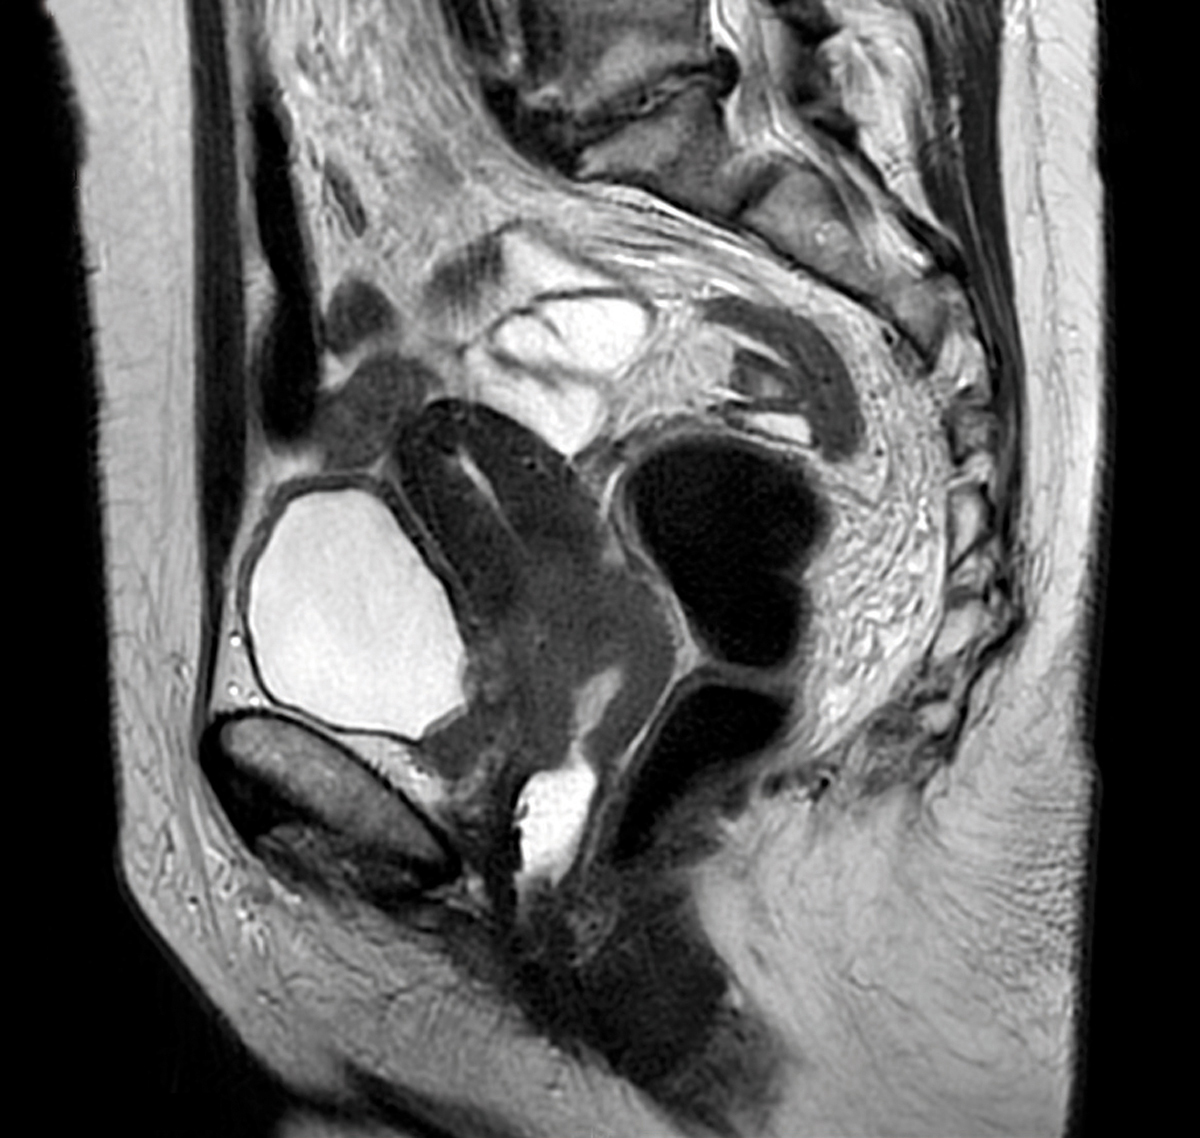

Il s'agit d'un aspect de cancer du col. Coupe sagittale en pondération T2 montrant une volumineuse tumeur du col mesurant 42 mm envahissant le myomètre et la vessie sous la forme d'un épaississement segmentaire en signal intermédiaire T2 de la paroi vésicale au niveau de plancher. L’examen se fait après opacification vaginale. Les tumeurs sont détectées à partir du stade IA2 (5 mm) et sont mesurées de façon tridimensionnelle sur les séquences pondérées en T2. L’envahissement du vagin (2/3 supérieurs ou 1/3 inférieur) se diagnostique par l’épaississement de la paroi avec une perte de l’hyposignal T2 normal. La même sémiologie est retrouvée concernant l’envahissement de la paroi vésicale ou rectale.